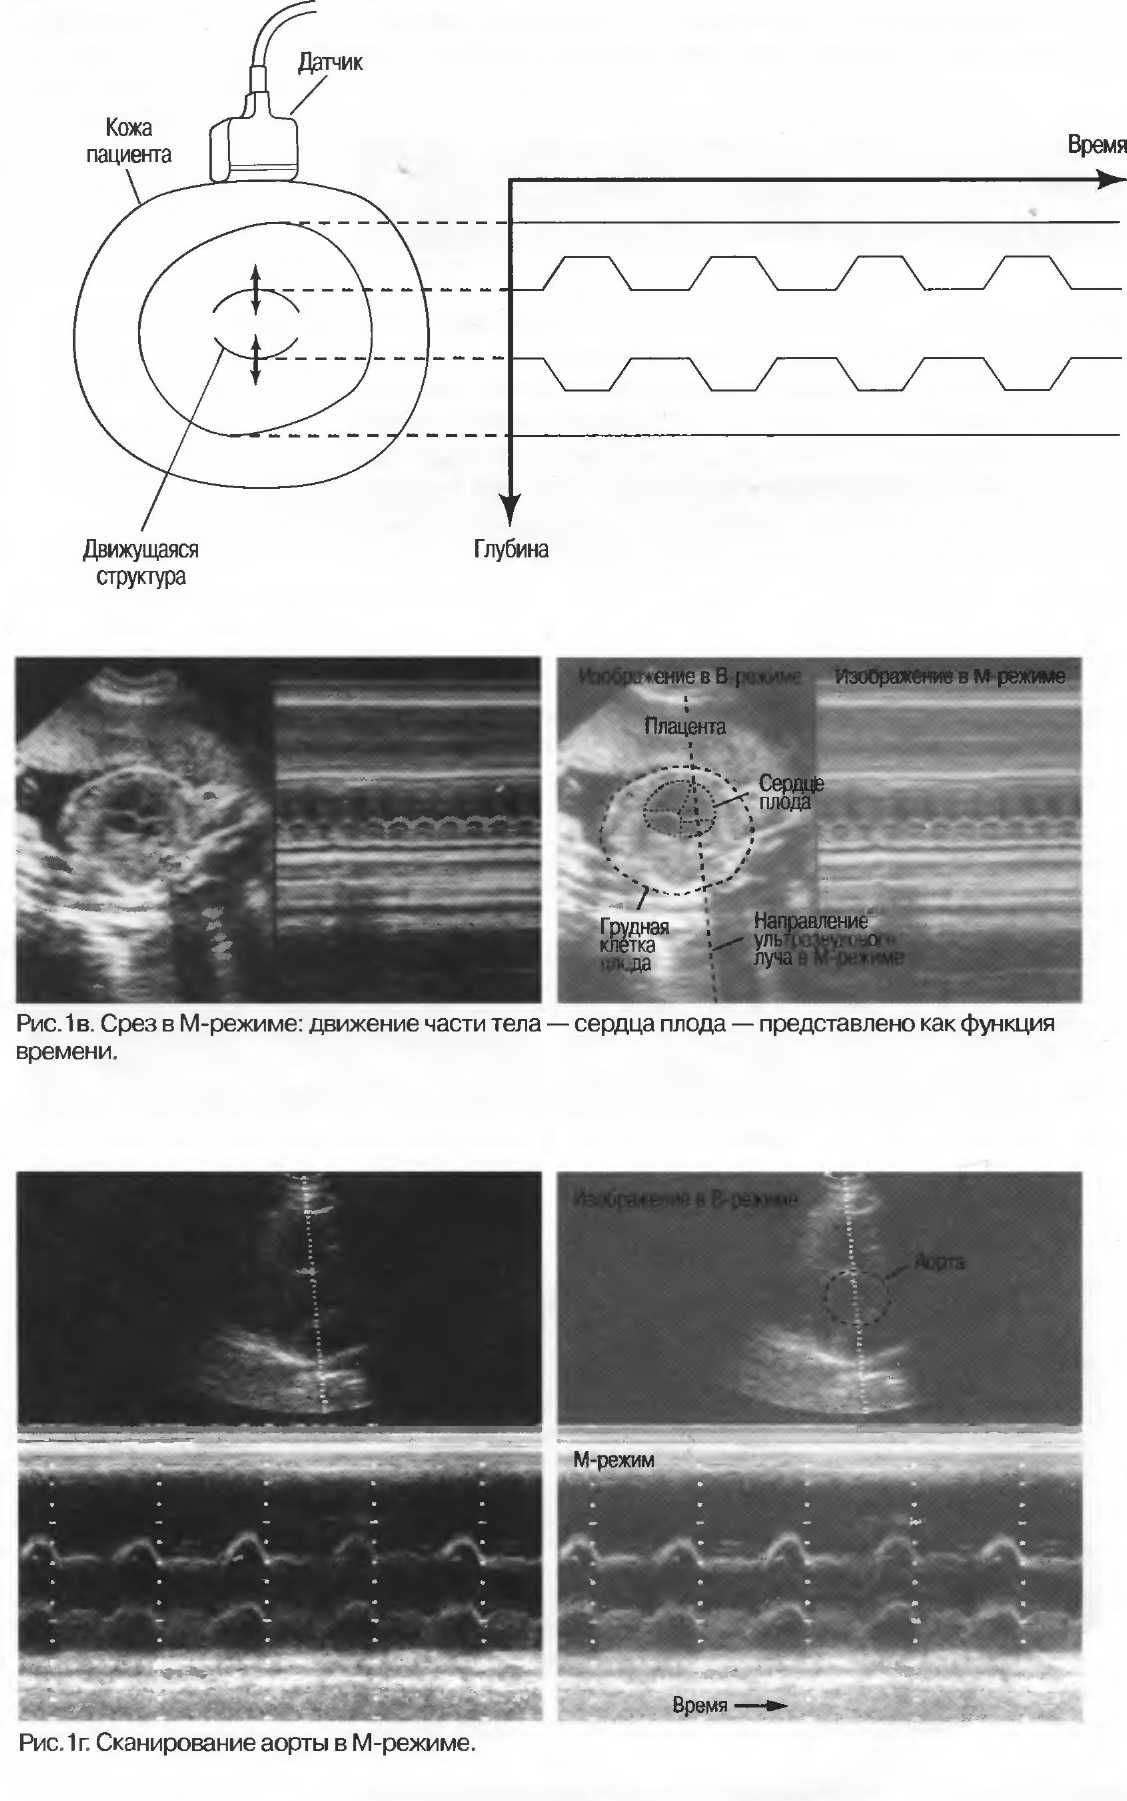

4. М-режим является еще одним способом отображения движения. В результате получается волнистая линия. Этот режим обычно используется в кардиологии (рис. 1в).

М-режим: |

показывает движение как функцию времени. Используется в кардиологии. |